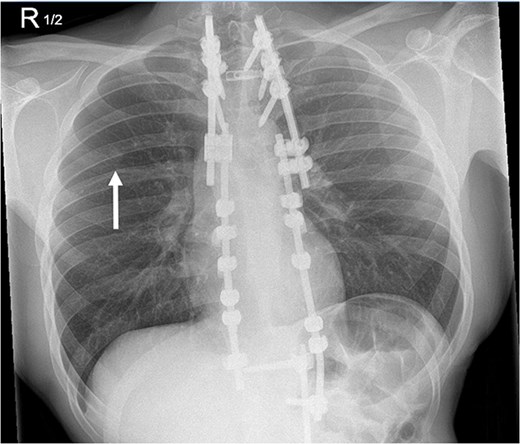

Subsequent computed tomography (CT) scan and positron emission tomography (PET) scan (Figs 2 and 3) confirmed the presence of three nodules in the right lung, suspicious for sarcoma metastases. An anterior, pleural-based upper lobe lesion, a posterior lower lobe lesion, and a lesion located at the bifurcation of his right middle and lower lobes.

Transverse and saggital views of the three nodules identified on an investigative CT scan.